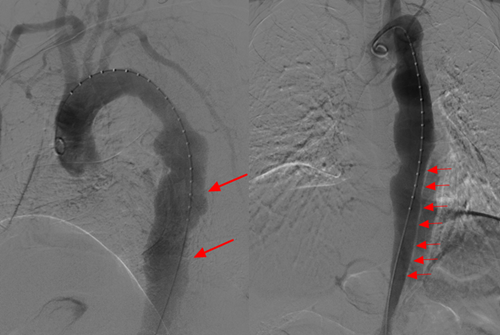

术中主动脉造影提示:胸降主动脉夹层动脉瘤形成,管壁凹凸不平,破口位于降主动脉,可见明显内膜分割影,将主动脉分为真腔、假腔。

随即,在介入科主任冯建新的指挥下,立即启动手术,急诊行主动脉夹层腔内隔绝术。冯建新手术团队精准的为患者两段式置入单分支一体支架(castor)+直形主体支架,近端破口完全封堵,无造影剂及内漏形成,左侧锁骨下动脉血流通畅,远端腹主动脉血流完全打开。

术前、术后主动脉CTA对比显示,肠系膜上动脉血流大部分再通,患者急性肠缺血症状明显缓解。